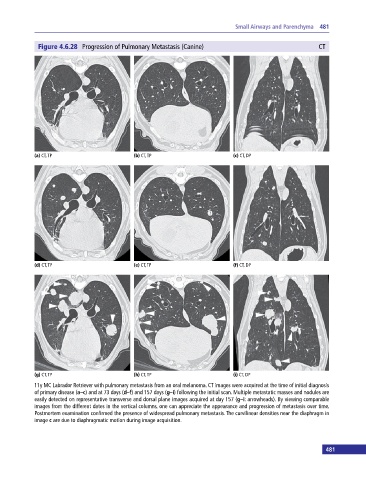

Figure 4.6.28 Progression of Pulmonary Metastasis (Canine) CT

(a) CT, TP (b) CT, TP (c) CT, DP

(d) CT, TP (e) CT, TP (f) CT, DP

(g) CT, TP (h) CT, TP (i) CT, DP

11y MC Labrador Retriever with pulmonary metastasis from an oral melanoma. CT images were acquired at the time of initial diagnosis

of primary disease (a–c) and at 73 days (d–f) and 157 days (g–i) following the initial scan. Multiple metastatic masses and nodules are

easily detected on representative transverse and dorsal plane images acquired at day 157 (g–i: arrowheads). By viewing comparable

images from the different dates in the vertical columns, one can appreciate the appearance and progression of metastasis over time.

Postmortem examination confirmed the presence of widespread pulmonary metastasis. The curvilinear densities near the diaphragm in

image c are due to diaphragmatic motion during image acquisition.